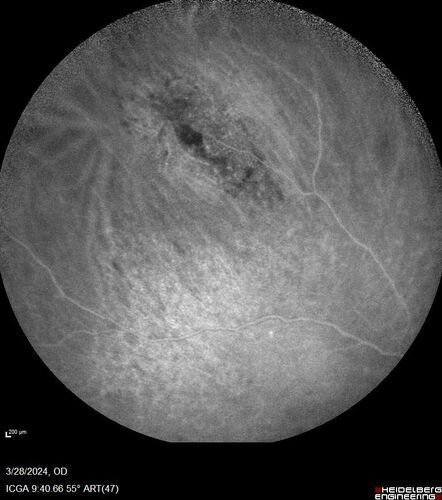

Serous Macular Detachment from Small Choroidal Melanoma

72 year old female misdiagnosed as CSR who had small choroidal melanoms.